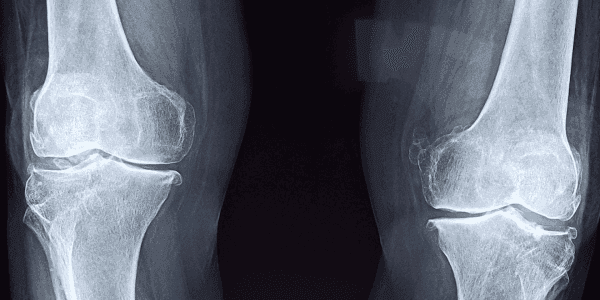

Bij artrose ontstaan er gaten in het kraakbeen, de schokdemper van een gewricht. Niet alleen oudere mensen krijgen artrose; ook bij jongeren kunnen kraakbeenschade oplopen, bijvoorbeeld na een val. Mensen met artrose kunnen zich minder goed bewegen en hebben vooral pijn. Er bestaan meerdere behandelingen om de pijn te verminderen, zegt professor dr. Marcel Karperien, wetenschappelijk directeur van Hy2Care. Het nadeel is dat ze maar voor een bepaalde tijd werken en of tamelijk ingrijpend zijn, zoals een operatie waarbij het kniegewricht vervangen wordt.

In de afgelopen jaren ontwikkelden Karperien en zijn team een duurzame oplossing, een vloeibare hydrogel die de gaten in het kraakbeen vult. “De gel werkt als een tweecomponentenlijm. Hij is vloeibaar als hij in de knie gespoten wordt, maar wordt daarna hard. Bovendien stimuleert de gel het lichaam om zelf weer kraakbeen aan te maken. Eenmaal hard vormt de gel een raamwerk waar kraakbeencellen tegenaan kunnen groeien. Dit zorgt voor een volledig herstel van beschadigde kraakbeen en pakt de oorzaak van de pijn daadwerkelijk aan.”Het aanbrengen van de gel gebeurt tijdens een kijkoperatie. Daarna mag de patiënt meteen naar huis. Dat maakt een behandeling met hydrogel veel minder pijnlijk en vergaand dan een vervangende knieoperatie. Nadat de werking van de gel in het laboratorium was aangetoond, vroeg Hy2Care DEFRO-subsidie aan. Het bedrijf vormde daarvoor een samenwerkingsverband met Baat Medical Products uit Hengelo, een ontwikkelaar van orthopedische producten en het TechMed centrum van de Universiteit Twente.